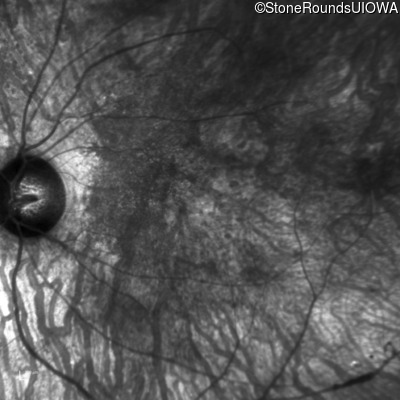

Infrared Fundus Photograph - Right - 20/200 +2

Exemplar